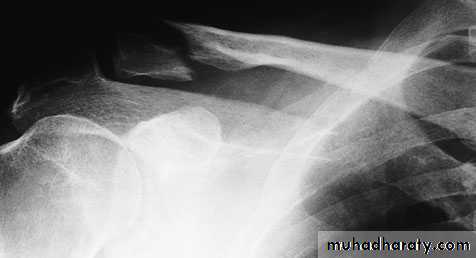

Imaging:

requires at least an AP view and another taken with a 30 degree cephalic tilt.middle third of the bone

Fractures of the outer third may be missed

medial third fractures it is also wise to obtain x-rays of the sterno-clavicular joint